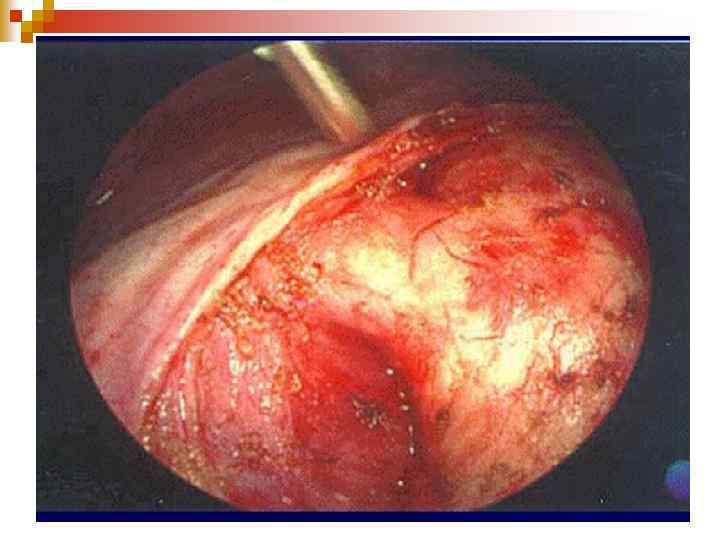

Оперативне лікування: n Паліативна операція (Blalock. Taussing): ь Створення анастомозу між підключичною артерією і ЛА. n Радикальна: як другий етап через 2 -3 роки після паліативної: усунення стенозу та пластика ДМШП.

Thomas-Blalock-Taussig Shunt Vivien Thomas Alfred Blalock Helen Taussig Vivien Thomas, Partners of the Heart, 1998 and Something the Lord Made - Best Made-for-TV Movie, 2004

November 29, 1944 Thomas-Blalock-Tuassig

Dr. Blalock does the Blalock (Johns Hopkins)

Systemic to Pulmonary Shunts